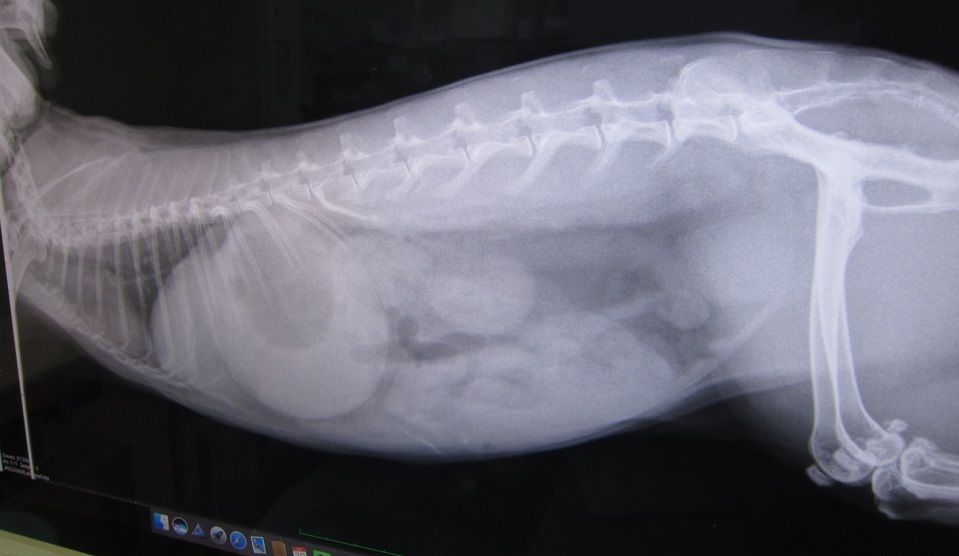

その後も糞はいくつか出てたが食べる方がまったくだったので連行

キャリーがイヤなのか、もしくは相当弱ってるのか、や、痛みに俄然弱いタイプかも?

ので、さすがに胃の張りとかはない

体重は1.96kgで甘えたさんは全開

異変から改善なく通院コースになるのも珍しく、

まあせっかく来たし?点滴もしてもらいました。

ステロイドも少しだけ。